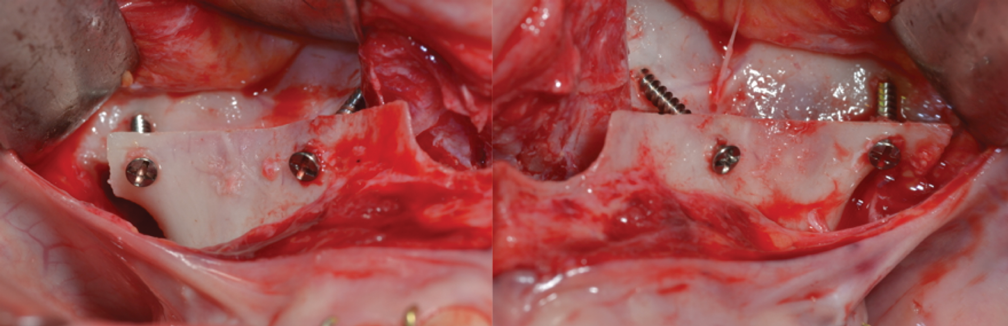

Fig 14. Surgical maxillary advancement with a two-piece Le Fort I osteotomy, performed after orthodontic decompensation. Right and left osteotomies are shown.

Figure 14